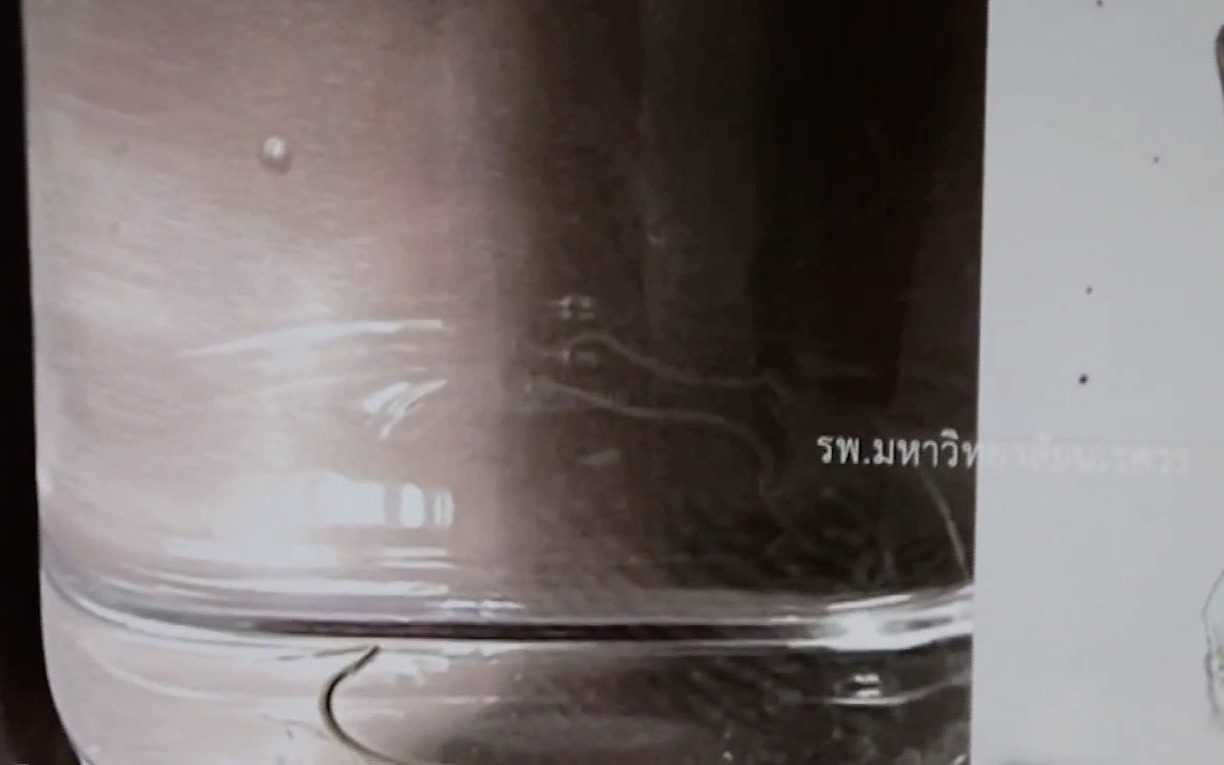

ด้านนายแพทย์คณินท์ กล่าวว่าหลังจากได้รับเคสผู้ป่วยมา ก็รักษาด้วยการให้ยาฆ่าพยาธิและยาลดอักเสบ จากนั้นผ่าตัดออกโดยใช้เวลาประมาณ 1 ชั่วโมง จากการตรวจสอบพบว่าเป็นพยาธิปอดหนู ความยาวประมาณ 0.5 ซม.